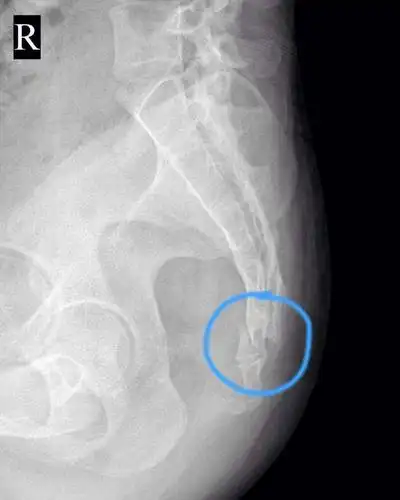

可致瘫痪!均安一学生尾椎痛,这种病要重视

骶髂关节炎主要疼痛位置在腰部和骶尾部,疼痛为钝痛,可放射至尾

[脊柱精讲]令人坐立不安的尾椎骨疼痛到底该怎么治

一般女性更容易发病,疼痛经常发生在骶骨表面,骶骨深部,尾骨尖端,骶